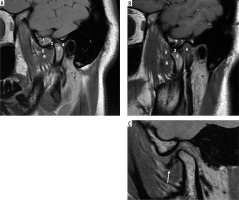

Case 2: Parotid lipoma

A 60-year-old male with painless left facial swelling. Axial MRI images of the head and neck region, showing a lesion in the left masticator space; well-defined lobulated mass of the left parotid gland. On MRI, because lipoma is composed of mature fat, it typically appears hyperintense on both T1-weighted and T2-weighted sequences. It closely follows the signal intensity of subcutaneous fat and will lose signal on fatsuppressed sequences (Figures 5A-B).

Figure 5

Axial section of MRI of parotid lipoma. A) T1-weighted MRI image – note the hyperintensity of the lesion on left parotid gland. B) T2-weighted MRI image – note the hyperintensity of the lesion. C) T1 C+ Fat sat – note the hypointensity of the lesion. These signal characteristics are consistent with a benign lipomatous lesion, which aids in preoperative differentiation from other malignant parotid tumours [Courtesy: Radiopaedia. DOI: https://doi.org/10.53347/rID-184951, rID: 184951]